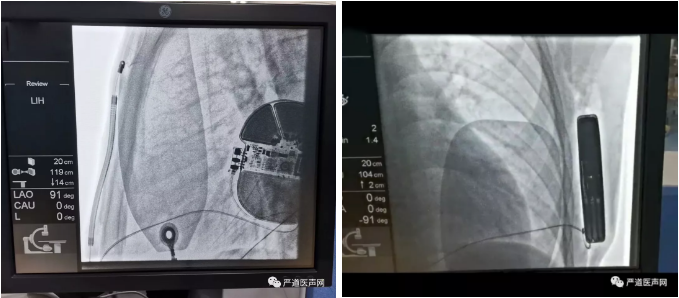

术后影像:

术中行DFT测试,S-ICD正确识别室颤后成功除颤转复为窦律,除颤能量65焦耳,除颤阻抗50欧姆。